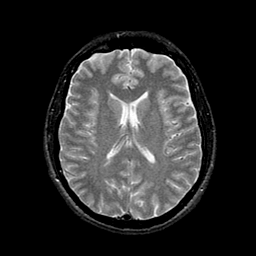

Tour 1: Next/Previous/Start: These images show typical findings in AIDS dementia: patchy hypoperfusion with a multifocal distribution which tends to be seen prominently in the frontal lobes. Compare with normal. Defects in cerebral perfusion have been previously reported in HIV positive individuals by single photon emission computed tomography (SPECT)[Masdeu, 1989 ][Pascal, 1991 ][Pohl, 1988 ][Holman, 1992 ][Schielke, 1990]. The anatomic and clinical significance of these findings, however, has remained uncertain. Because previous studies have shown that AIDS dementia complex (ADC) is associated with both functional defects and structural evidence of brain volume loss, we spatially matched (registered) the functional and structural data to assess the extent to which observed perfusion defects were "real", that is, represented low tracer uptake from structurally normal brain. The image datasets shown here are sampled along the same plane of view, to permit the direct comparison of SPECT and MR images in ADC. This type of analysis shows that there are functional defects (ie perfusion defects) in areas that appear non-atrophic. These are perhaps sites of early damage in which the structural images are still relatively normal.